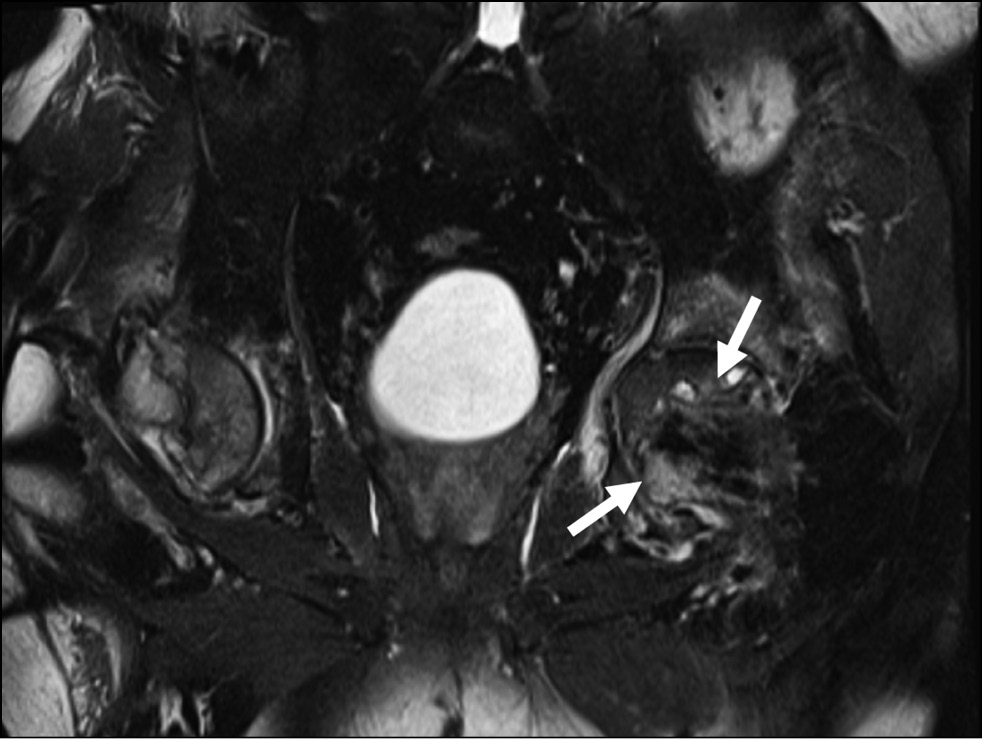

Aseptic necrosis is more common in patients with severe disease, with an incidence of 5% to 58%. Avascular bone necrosis is one of the adverse symptoms of SARS-CoV-2. Avascular necrosis can be detected from 7 days to 2 months from the onset of coronavirus. There was no relationship between the severity of SARS-CoV-2 and the onset of avascular necrosis. The lesion affects all major joints (hip, knee, shoulder, spinal joint, and sacrum), and can be diagnosed by MRI (Fig. 6, 7). Patients treated with corticosteroids for a long time or with higher doses had an increased risk of osteonecrosis [31, 32].

Fig. 6. Magnetic resonance imaging showing aseptic necrosis of the head of the left femur in a patient infected with coronavirus (arrows).